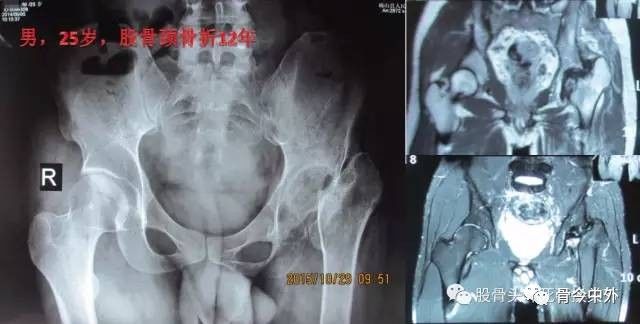

图19?男,25岁,股骨颈骨折一直拖延12年,跛行,病人自诉疼痛轻微跛行

图20? 上图25岁股骨颈骨折12年病人活动情况